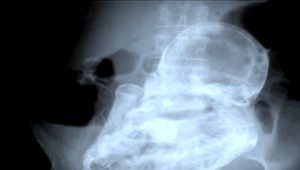

INDIANAPOLIS / Silné bolesti brucha priviedli do nemocnice mladú ženu. Netušila, že z nej neodíde sama. Návaly bolesti sa totiž ukázali byť tehotenskými kontrakciami.

Američanke môžu mnohé tehotné len závidieť. Celé tehotenstvo ani len netušila, že je v požehnanom stave a to už bola dvojnásobnou matkou. Žiadne nevoľnosti, nechutenstvo, ani pohyby. Napriek tomu na svet priviedla zdravého 3,5 kilového chlapčeka.

"Lekári mali najprv podozrenie na žlčové kamene. O pár minút jej praskla plodová voda," hovorí hrdý otec Josh Cox. "Vôbec som o tom netušila. Nemala som žiadne príznaky. Trochu som pribrala, ale to som pripisovala zime. Šokovalo ma to," dodáva čerstvá mamina Mandy Bachelor.